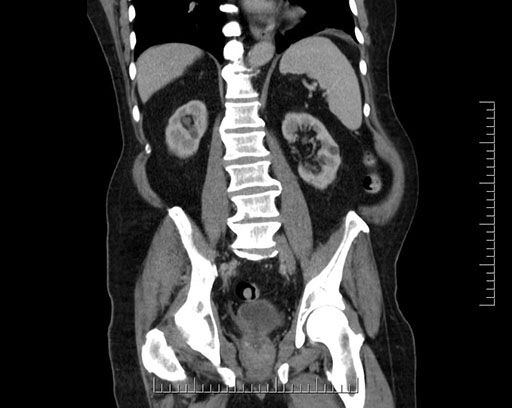

Whipple (pancreaticoduodenectomy) [case 7]

Imaging Analysis

Look through the patient's CT scan to identify any areas of concern for the necessary procedure.

Coronal - stented